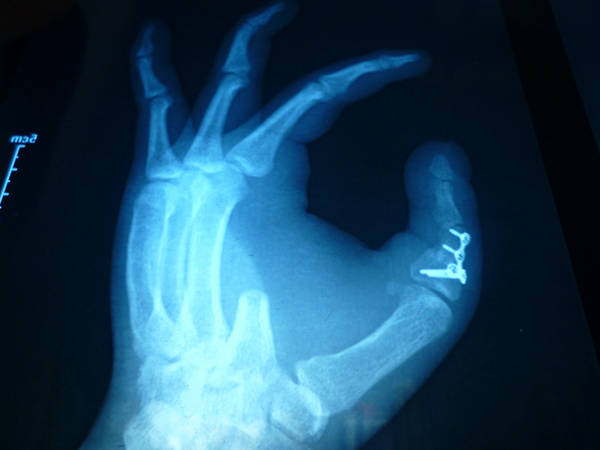

[手指再造] 拇再造术后供区的另一种修复(12.23随访照片来了)

1.jpg 2.jpg 3.jpg 4.jpg 5.jpg 6.jpg 7.jpg 8.jpg 9.jpg 10.jpg 11.jpg 12.jpg 13.jpg

功能和外观都很好,学习了,池主任的病人应该感到幸运和幸福